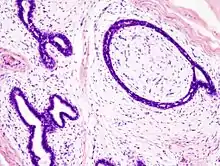

Fibroadenoma of the breast is a benign tumor composed of a biplastic proliferation of both stromal and epithelial components.[14][15] This biplasia can be arranged in two growth patterns: pericanalicular (stromal proliferation around epithelial structures) and intracanalicular (stromal proliferation compressing the epithelial structures into slit-like spaces).

These tumors characteristically display hypovascular stroma compared to malignant neoplasms.[16][17][11] Furthermore, the epithelial proliferation appears in a single terminal ductal unit and describes duct-like spaces surrounded by a fibroblastic stroma. The basement membrane is intact.[18]

Fibroadenoma histology (H&E). The image demonstrates intracanalicular morphology (bottom left) and pericanalicular morphology (top right)